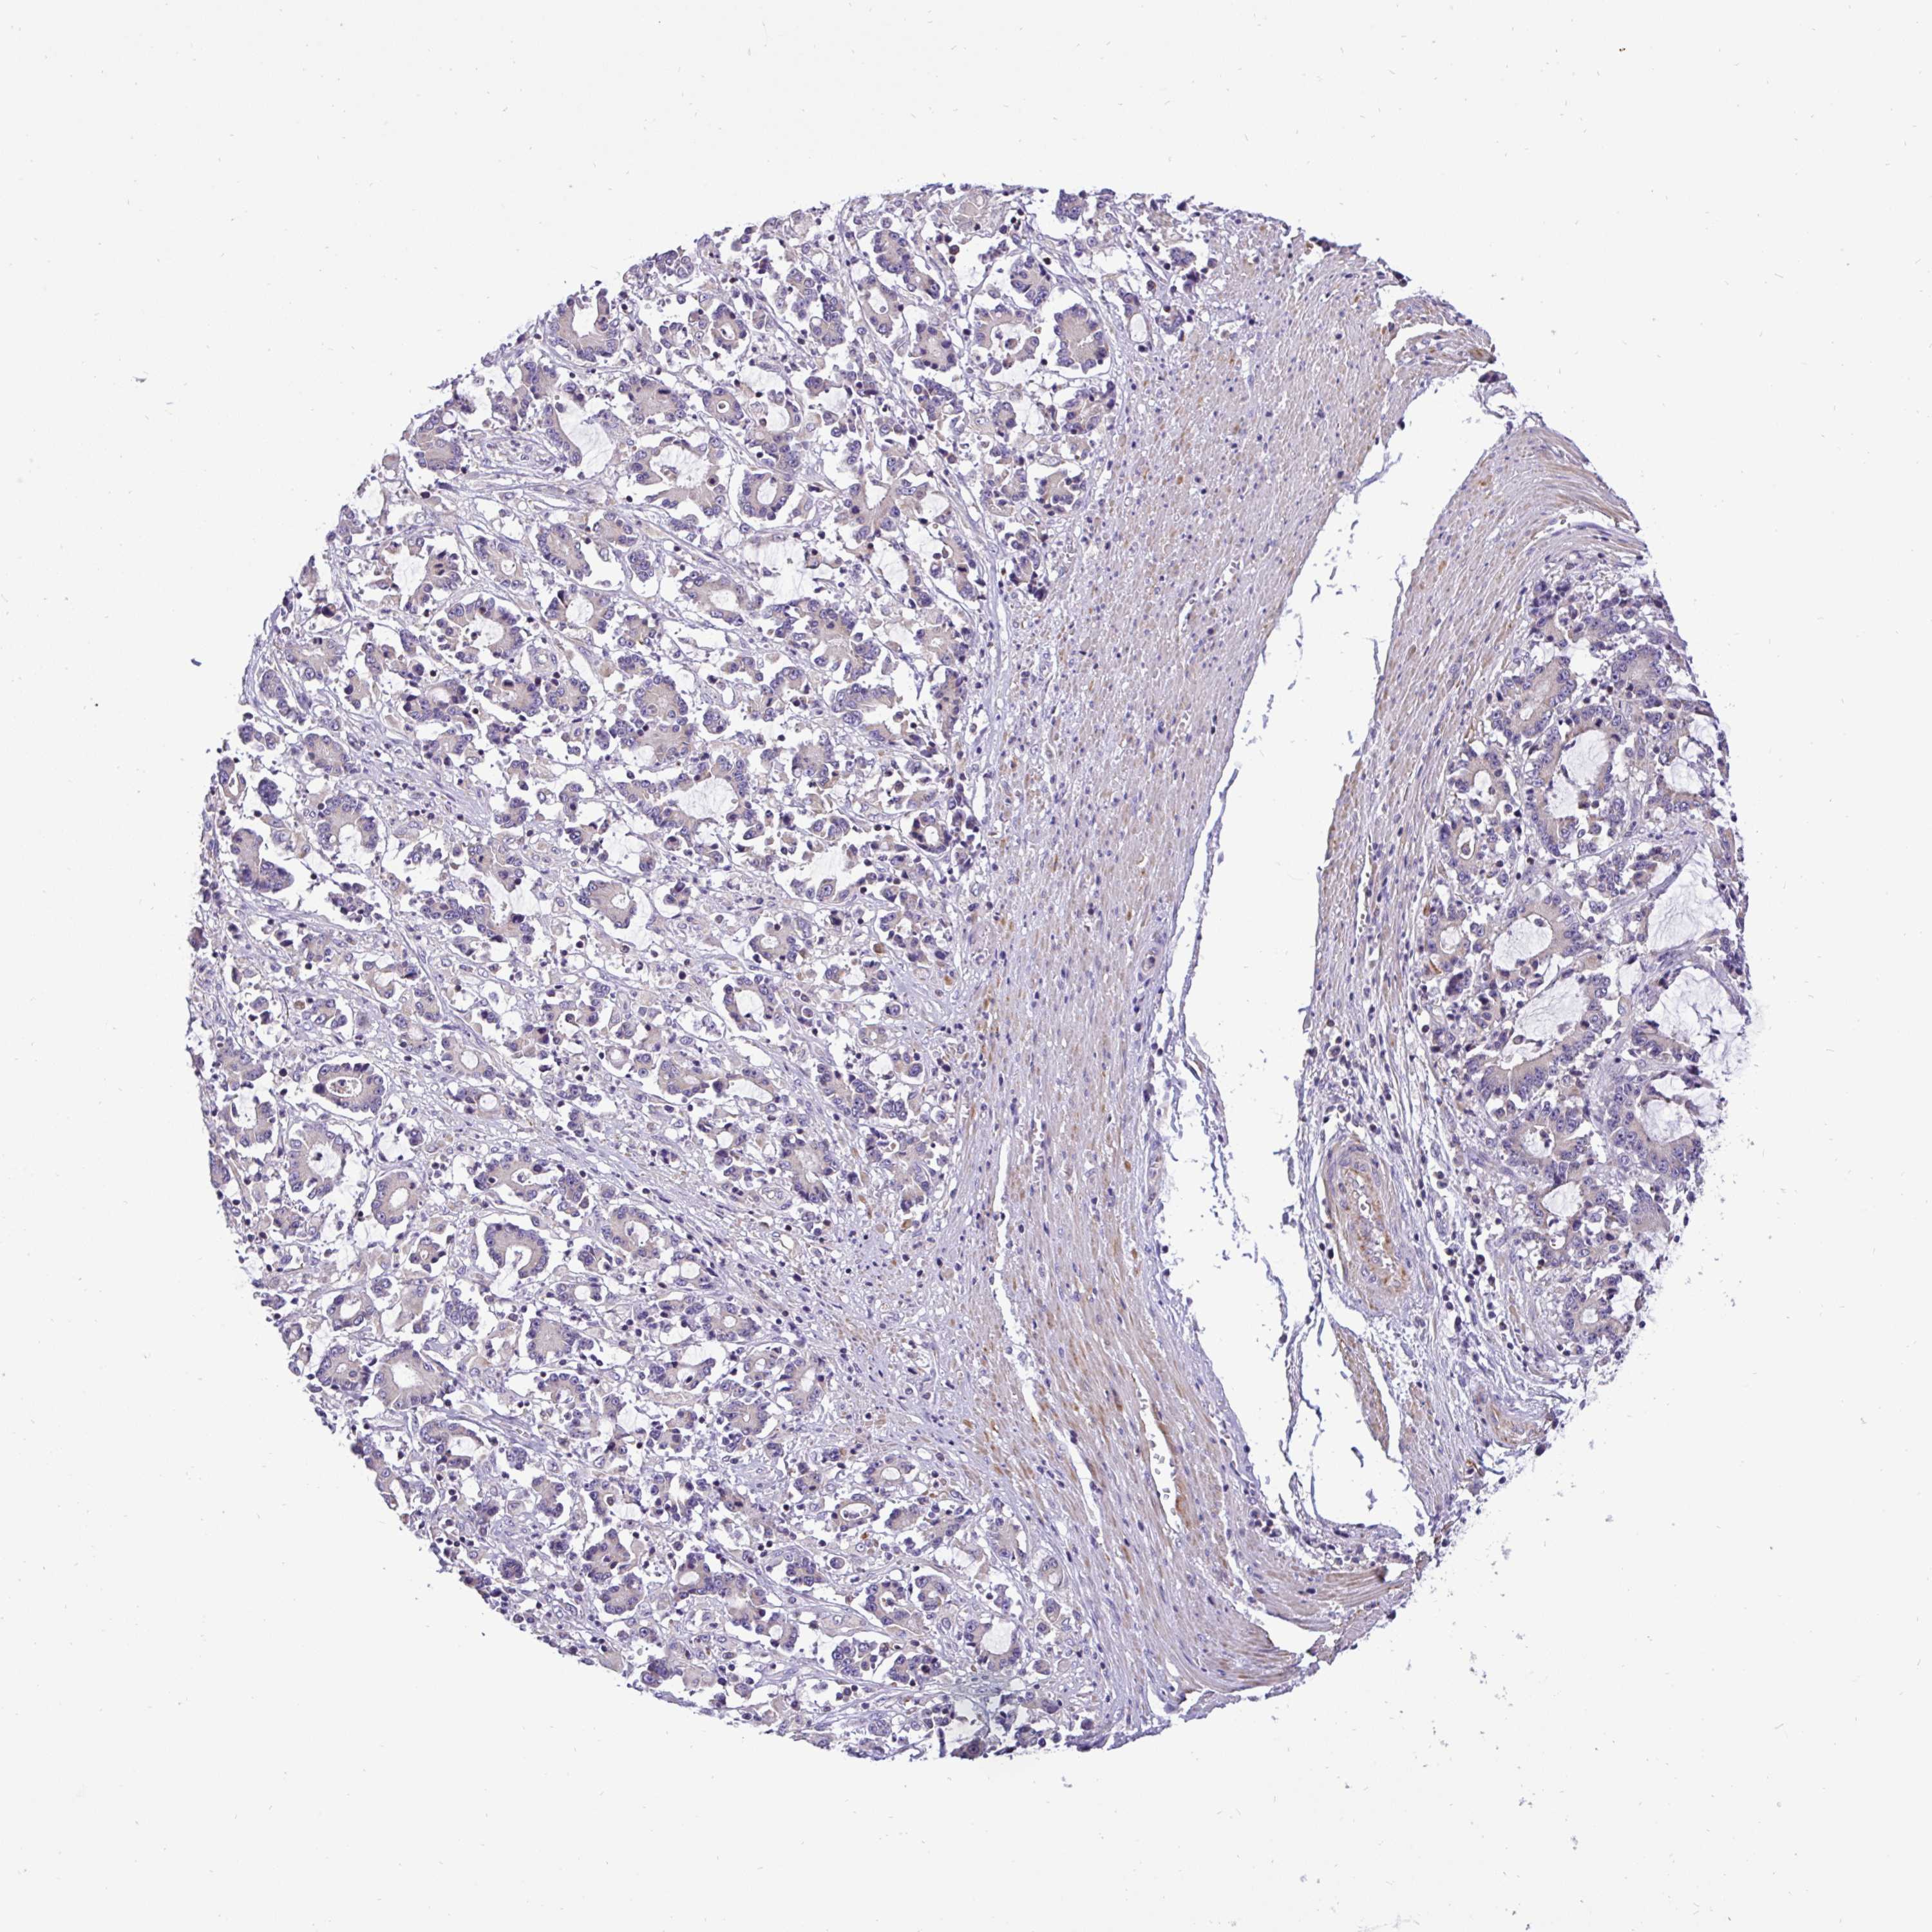

STOMACH CANCER - Protein expressioni

A mouse-over function shows sample information and annotation data. Click on an image to view it in a full screen mode. Samples can be filtered based on level of antibody staining by selecting one or several of the following categories: high, medium, low and not detected. The assay and annotation is described here.

Note that samples used for immunohistochemistry by the Human Protein Atlas do not correspond to samples in the TCGA dataset.

Antibody stainingi

Antibody staining in the annotated cell types in the current human tissue is reported as not detected, low, medium, or high, based on conventional immunohistochemistry profiling in selected tissues. This score is based on the combination of the staining intensity and fraction of stained cells.

Each image is clickable and will lead to virtual microscopy that enables deeper exploration of all samples and also displays staining intensity scores, fraction scores and subcellular localization as well as patient and tissue information for each sample.

Antibody HPA057267

Antibody HPA058086

Staining

High

Medium

Low

Not detected

Intensity

Strong

Moderate

Weak

Negative

Quantity

>75%

75%-25%

<25%

None

Location

Nuclear

Cytoplasmic/membranous

Cytoplasmic/membranous,nuclear

Adenocarcinoma, NOS